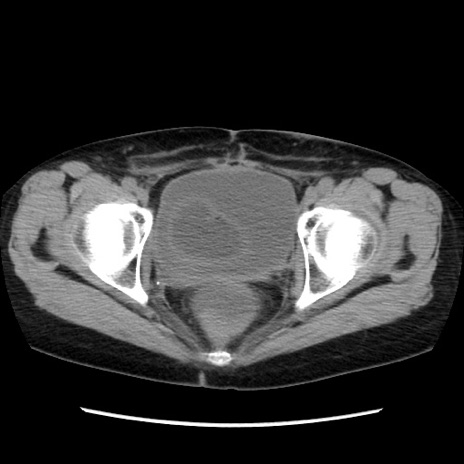

症例32(横断像)

【症例】40歳代 女性

【主訴】上腹部痛、嘔気・嘔吐

【現病歴】約9時間前頃から急に上腹部痛、嘔気、嘔吐が出現。改善しないため救急要請。

【既往歴】子宮頚癌(広汎子宮全摘術、放射線療法)、腸閉塞

【身体所見】腹部:平坦、軟、腸雑音亢進、上腹部を中心に腹部全体に圧痛あり。

【データ】WBC 8400、CRP 0.03